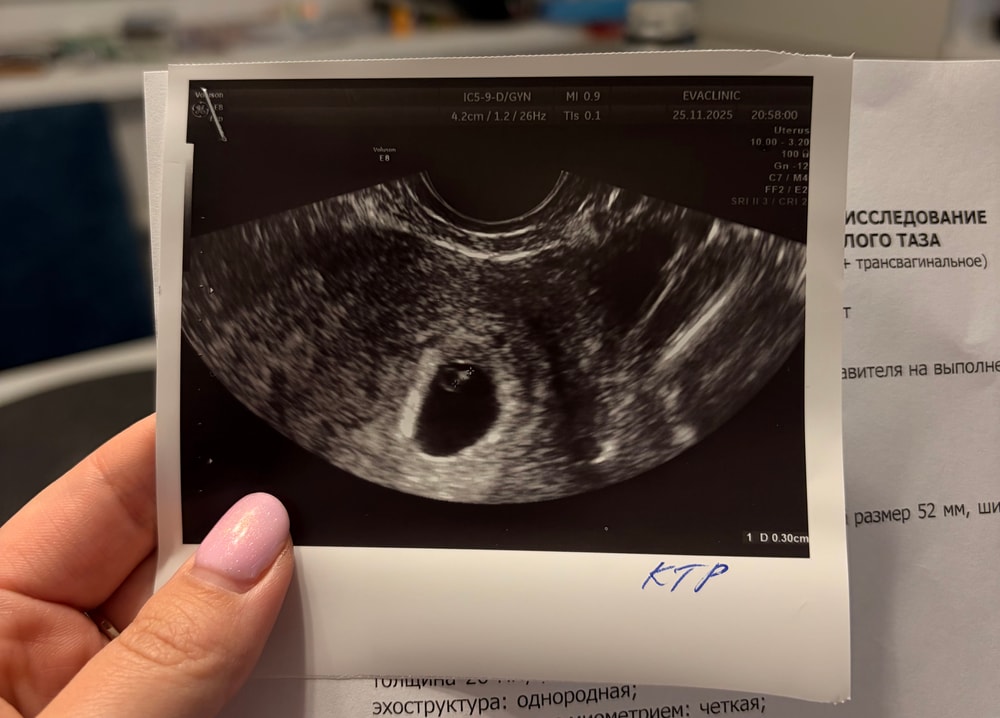

Осмотр в беременность, вопросыВчера писала, что на узи не увидели желточный мешочек и нашли миому.

Решила, что нужно сходить за еще одним мнением к другому врачу. Так вот мне показали мое «кольцо с бриллиантом». И также сказали, что никакой миомы нет.